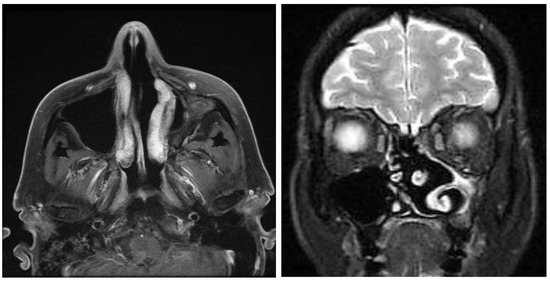

3.4. MRI